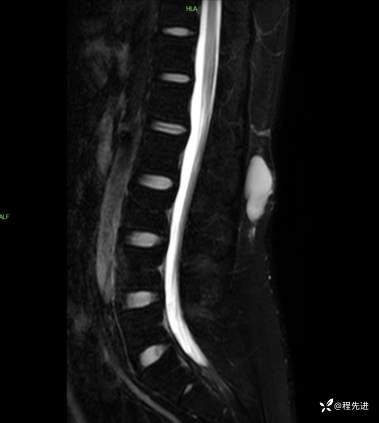

T2压脂矢状位: